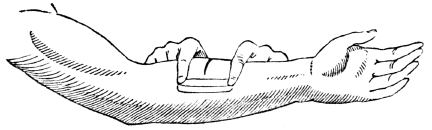

| 17. | Anatomy of the Circulatory Organs, | 154 |

| 18. | Physiology of the Circulatory Organs, | 164 |

| 19. | Hygiene of the Circulatory Organs, | 172 |

| 20. | Anatomy of the Lymphatic Vessels, | 181 |

| 20. | Physiology of the Lymphatic Vessels, | 183 |

| 20. | Hygiene of the Lymphatic Vessels, | 188 |